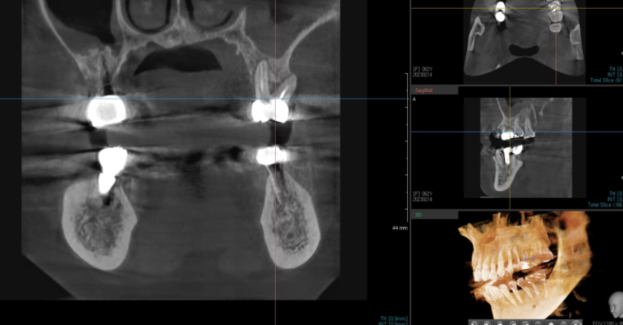

상악동까지 염증이 퍼졌는지 확인하기위해

3d-ct까지 촬영해 보았습니다.

상악동을 관찰하는데 ct만한게 없거든요~~

ct에서 상악동까지 염증이 번진 게 확인됩니다.

어금니 염증이 상악동염을 유발했네요.

치아로부터 원인이 발생하였다고 하여

"치성 상악동염"이라 불립니다.